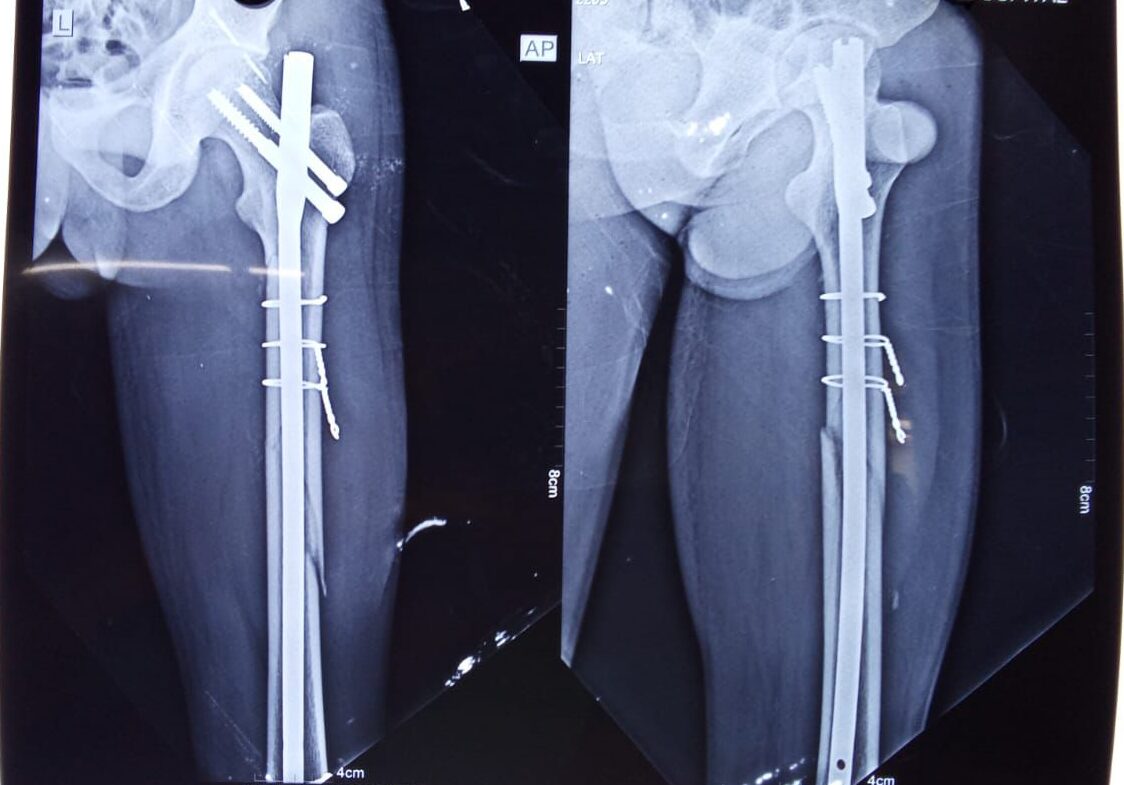

Moments That Mark Meaningful Recovery

Witness real patient transformations at The Ortho Clinic through images that reflect successful treatments and restored mobility.